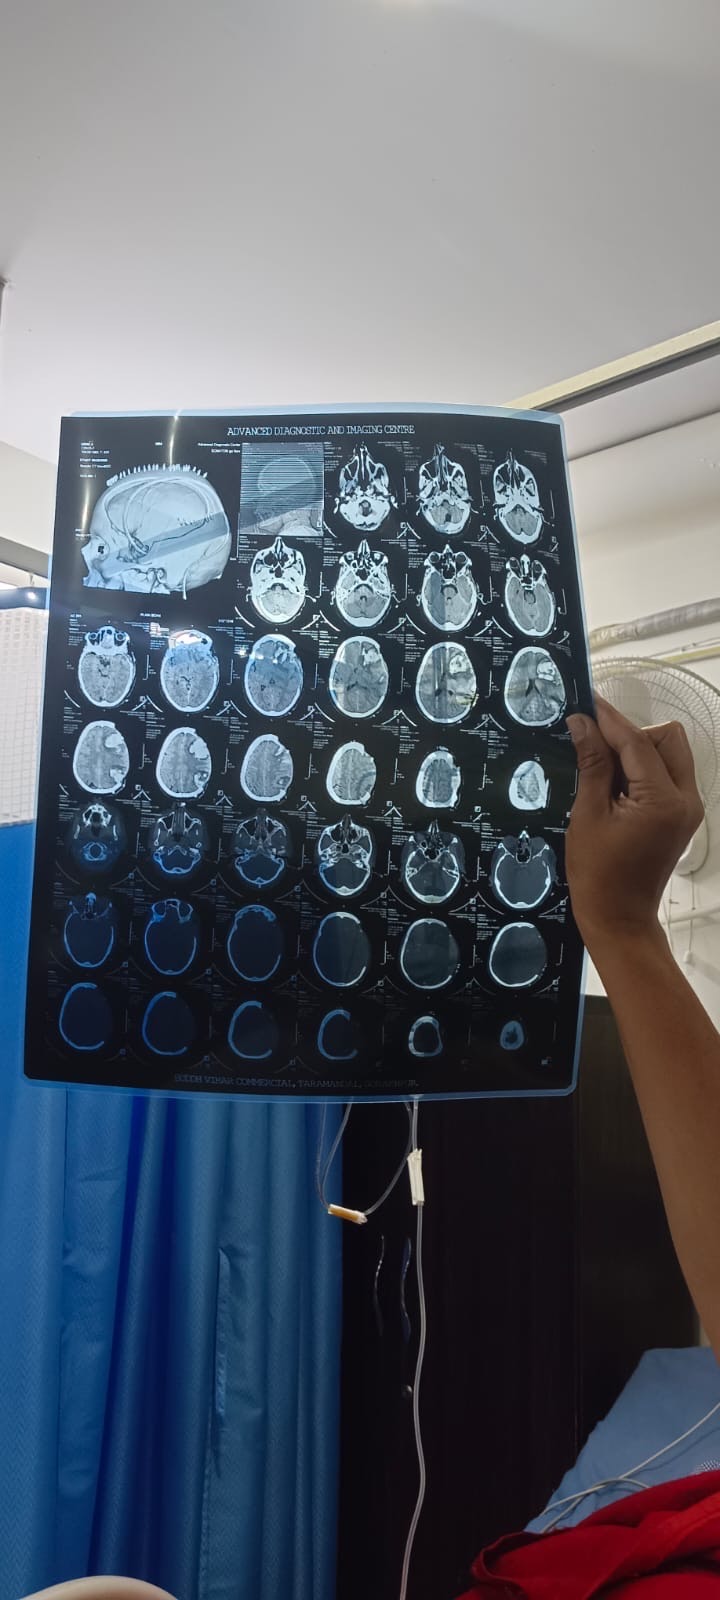

Urmila is a widow and recently met with a severe accident that caused a brain injury. She has two sons, aged 20 and 24, who together earn around $200 a month. They have already spent all their savings and are doing everything possible to support their mother’s treatment. However, the medical expenses are far beyond what they can afford.